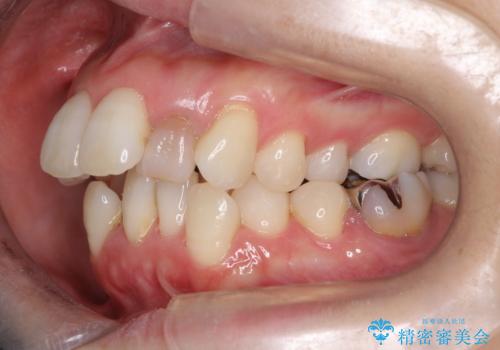

重度のガタガタと出っ歯をワイヤーによる抜歯矯正で整った歯並びへ

- 全体的ながたがたを主訴に来院されました。

上顎の前歯は前方に傾斜して、下顎の前歯は強いガタガタが見られました。

前から4番目の歯を上下左右合計2本抜歯して、歯並びを整える計画としました。